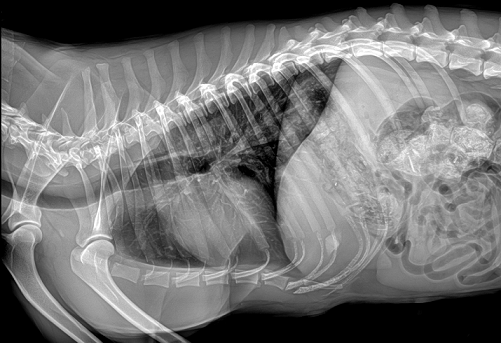

国产品牌普爱医疗宠物dr采用非晶硅平板探测器,可以令动物影像成像清晰而快速,基本上5s左右就能使动物影像清楚成像且无拖尾现象,而且分辨率高,极限空间分辨率可达到5.0Lp/mm;

普爱医疗宠物dr拍摄的高清照片

同时,宠物影像成像尺寸较大,成像尺寸可达43cm x 43cm,并且以DICOM格式储存数据,极大的方便了医疗工作者们追踪检查时使用。同时还支持窗宽、窗位、放大、旋转、正像和负像转换等显示功能。如果您想购买普爱医疗宠物dr,或了解具体技术参数,欢迎联系我们。